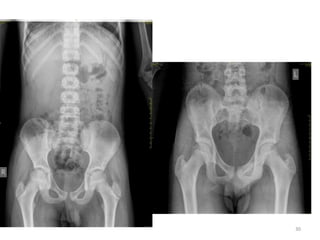

Practical issues:

• For age estimation, usually standard right sided

X-rays are taken in AP view

-with few exceptions elbow (AP and Lat)

• Selection of regions/joints:

for age 6-12 years  elbow and wrist

for age 13-16 years  elbow and pelvis

• Wrist (& hand) is most studied region by

foreign authors/researchers.